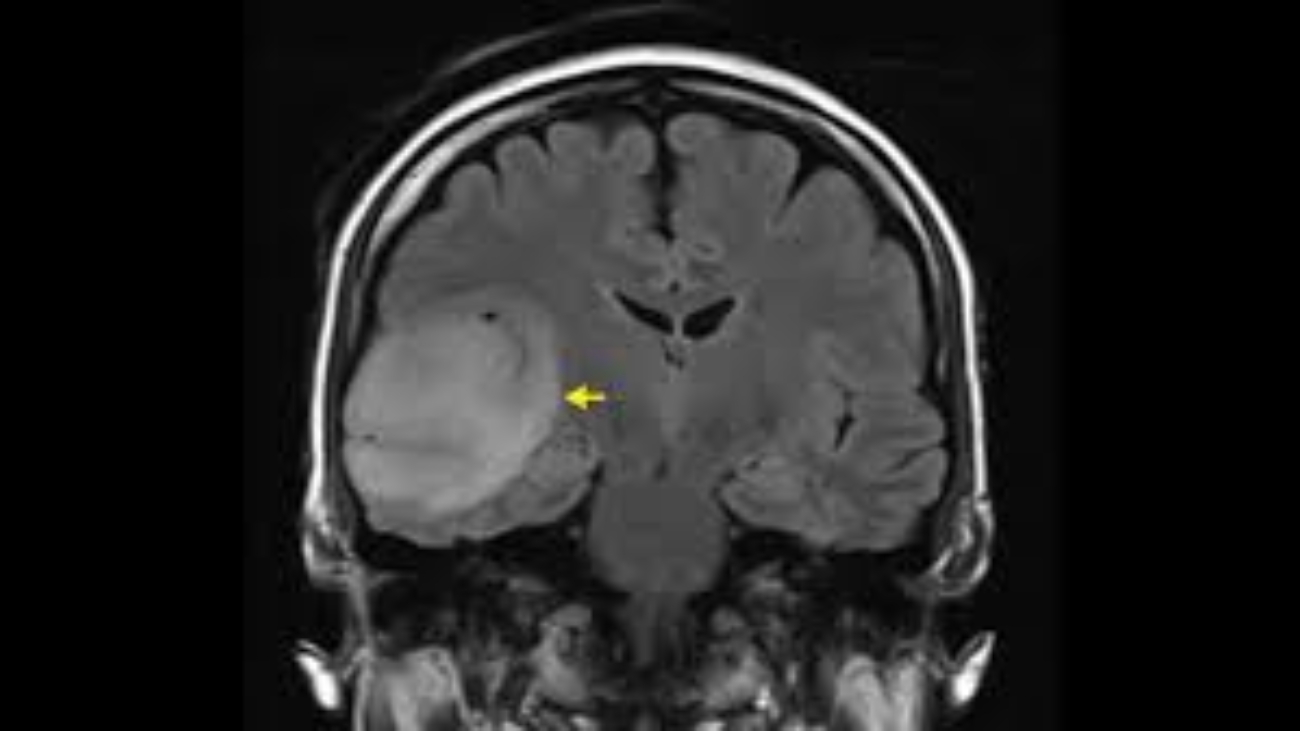

Doctors use specific and targeted neuroradiology techniques to trace internal brain connections. One common imaging method tracks water movement within the tissues, and this shows the actual nerve fibers. Water naturally moves along specific neural pathways, enabling specialized scanners to create a detailed map of the brain’s physical wiring.

This intricate mapping process requires highly specialized computer software. The computer carefully processes the raw scan data, and it builds a precise three-dimensional model of the nerves. After the computer model is complete, a clinical radiologist examines the rendered pathways to identify any unusual breaks. These resulting maps show structural pathways and functional activity. Structural maps display the physical nerve wires, while functional maps show brain activity over a specific period of time.

Some of the main technical tools used in these clinical exams include Magnetic Resonance Imaging (MRI) machines that capture deep tissue layers. There are also Computed Tomography (CT) scanners that provide rapid structural images and advanced computer modeling software that renders three-dimensional maps.